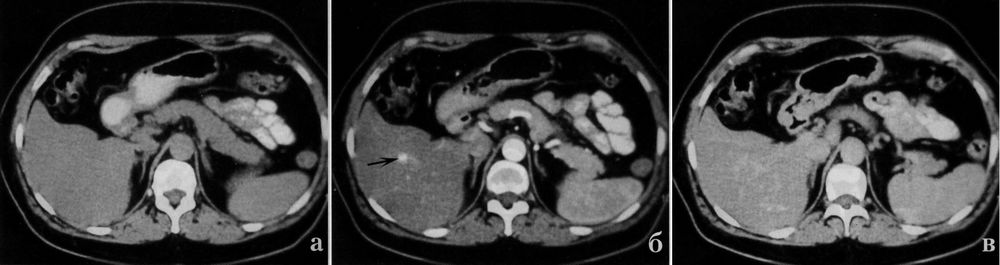

Капиллярная гемангиома печени на КТ имеет однородную структуру, что вызывает трудности выявления ее на компьютерных томограммах, в то время как при УЗИ эта опухоль хорошо визуализируется. При контрастном усилении капиллярные гемангиомы начинают окрашиваться в артериальную фазу, в венозную фазу их окрашивание нарастает, в отсроченную венозную фазу они остаются гиперденсивными относительно паренхимы (фото КТ выше).

Симулировать гемангиому может аномальное развитие сосудов, представляющее артериовенозную мальформацию. Эта аномалия также проявляется в артериальную фазу контрастного усиления ярко окрашенным очагом, но интенсивность его быстро убывает в последующие фазы исследования (фото КТ выше).